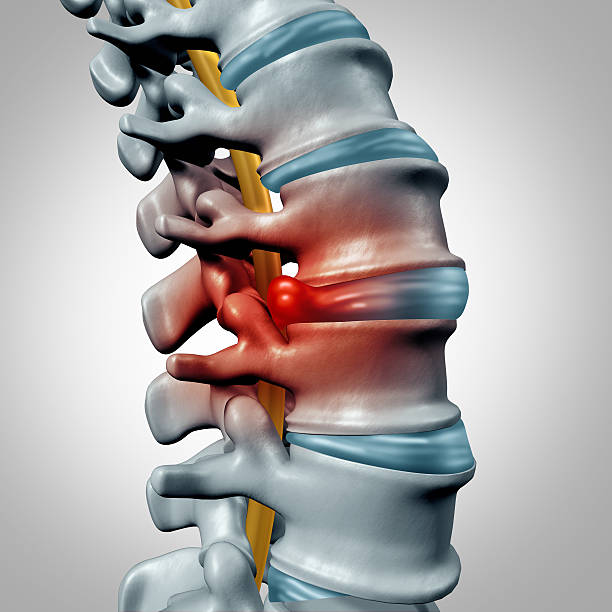

Sente dor na coluna, formigamento, dormência ou sensação de peso na perna?

Nosso tratamento é específico para hérnia de disco com uma avaliação minuciosa, identificando a causa exata do seu problema.

Aplicamos técnicas modernas e personalizadas, proporcionando resultados duradouros, liberdade de movimento sem dor e uma vida mais ativa e sem limitações.

Até 90% das hérnias de disco podem ser tratadas de forma conservadora, com resultados duradouros e sem riscos cirúrgicos.